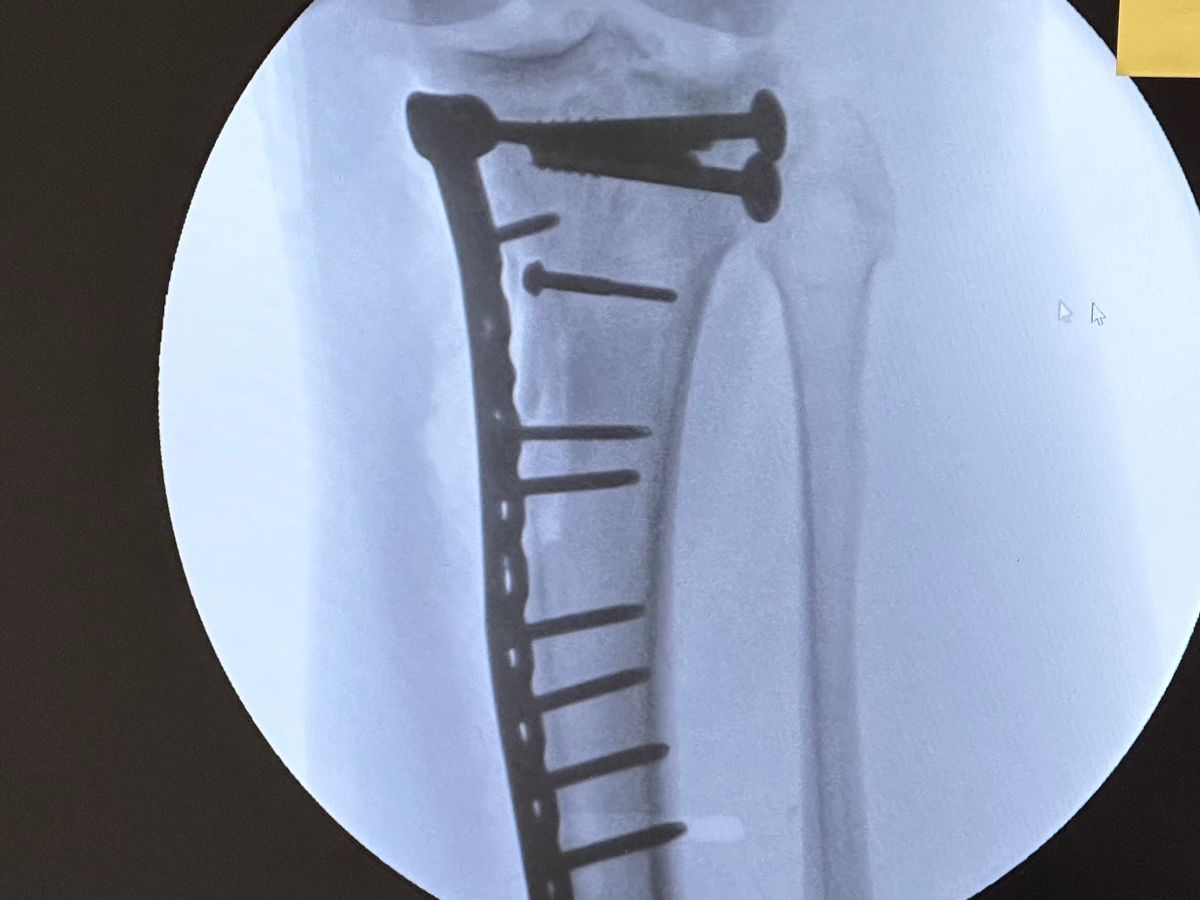

Hey all I was really not wanting to do this but I have come to a point where I really need helpI learned today that I will not be able to add weight to my leg for another 3 months♂️which is totally screwing me on work and with me not working bills are falling behind so if there is anyway way you can help me and my family out it would be greatly appreciated